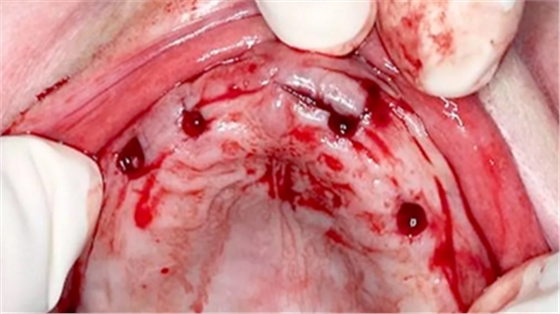

根據(jù)CBCT數(shù)據(jù)和石膏模型掃描數(shù)據(jù)進(jìn)行數(shù)字化3D種植方案設(shè)計及種植手術(shù)導(dǎo)板設(shè)計(coDiagnostixTM)(圖2),通過3D打印技術(shù)制作外科手術(shù)導(dǎo)板,同時將引導(dǎo)型套筒固定在導(dǎo)板中(圖3)。

(圖2)